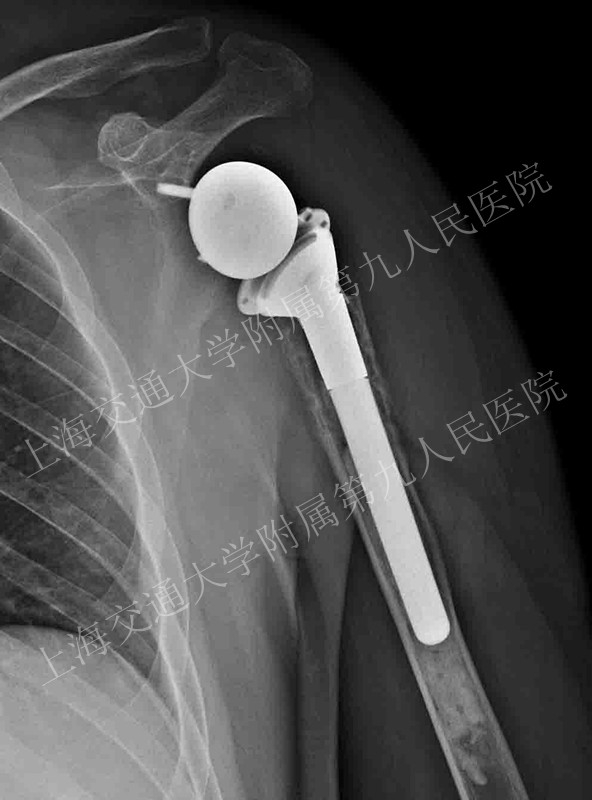

术后效果